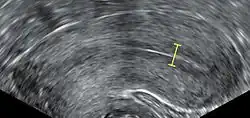

The eggs are retrieved from the patient using a transvaginal technique called transvaginal ultrasound aspiration involving an ultrasound-guided needle being injected through follicles upon collection. Through this needle, the oocyte and follicular fluid are aspirated and the follicular fluid is then passed to an embryologist to identify ova. It is common to remove between ten and thirty eggs. The retrieval process, which lasts approximately 20 to 40 minutes, is performed under conscious sedation or general anesthesia to ensure patient comfort. Following optimal follicular development, the eggs are meticulously retrieved using transvaginal ultrasound guidance with the aid of a specialised ultrasound probe and a fine needle aspiration technique. The follicular fluid, containing the retrieved eggs, is expeditiously transferred to the embryology laboratory for subsequent processing.[55]